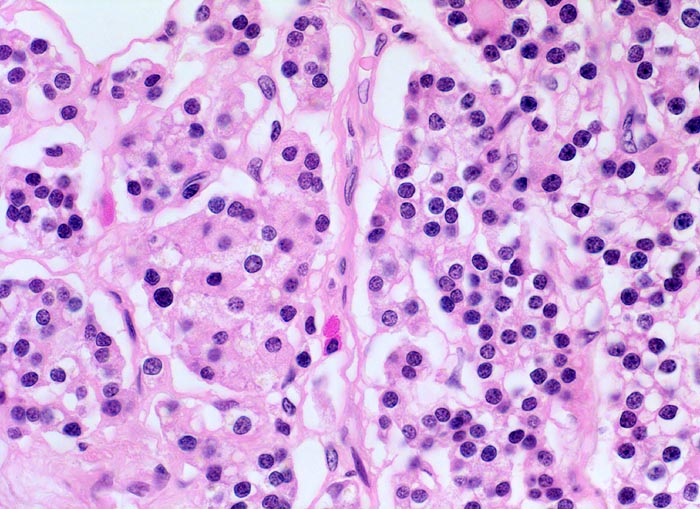

Morphologisch besteht bei sHPT eine Hauptzellhyperplasie. Makroskopisch findet sich eine meist ungleich ausgebildete Vergrösserung aller Nebenschilddrüsen. Die Grösse der Drüsen entspricht der Schwere und der Dauer des Stimulus. Die im früheren Stadium gefundene diffuse Hyperplasie mit Ersatz des Stromas und der Fettzellen durch chronisch stimulierte Hauptzellen (> 558) (> 559) geht im späteren Stadium in eine noduläre Hyperplasie („Pseudoadenome“) über (> 2358). Die regulierte Anpassung der Nebenschilddrüsen kann in eine Autonomie übergehen (tHPT) (> 3704). Morphologisch besteht in diesem Fall eine unregelmässige noduläre Hyperplasie. Gelegentlich entwickelt sich beim tHPT ein dominanter Knoten, der morphologisch nicht von einem Adenom bei pHPT unterscheidbar ist.

• Knotige vergrösserte Nebenschilddrüse. Abgrenzung der einzelnen Knoten durch breite Fibrosebänder.

• Hyperplasie lipidarmer Hauptzellen.

• Areale mit oxyphilen Zellen.

• Verminderter Fettgehalt (<<35%). Für normale Nebenschilddrüsen gilt: